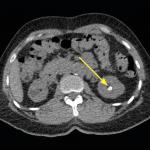

Cystite emphysémateuse

Une patiente de 89 ans, sans antécédent majeur, consulte aux urgences à la suite d’une chute accidentelle avec fracture...